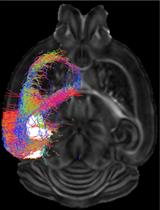

利用弥散磁共振成像绘制小鼠大脑的宏观结构和连接组图

Macroscopic Structural and Connectome Mapping of the Mouse Brain Using Diffusion Magnetic Resonance Imaging

Translational work in rodents elucidates basic mechanisms that drive complex behaviors relevant to psychiatric and neurological conditions. Nonetheless, numerous promising studies in rodents later fail in clinical trials, highlighting the need for improving the translational utility of preclinical studies in rodents. Imaging of small rodents provides an important strategy to address this challenge, as it enables a whole-brain unbiased search for structural and dynamic changes that can be directly compared to human imaging. The functional significance of structural changes identified using imaging can then be further investigated using molecular and genetic tools available for the mouse. Here, we describe a pipeline for unbiased search and characterization of structural changes and network properties, based on diffusion MRI data covering the entire mouse brain at an isotropic resolution of 100 µm. We first used unbiased whole-brain voxel-based analyses to identify volumetric and microstructural alterations in the brain of adult mice exposed to unpredictable postnatal stress (UPS), which is a mouse model of complex early life stress (ELS). Brain regions showing structural abnormalities were used as nodes to generate a grid for assessing structural connectivity and network properties based on graph theory. The technique described here can be broadly applied to understand brain connectivity in other mouse models of human disorders, as well as in genetically modified mouse strains.Graphic abstract: Pipeline for characterizing structural connectome in the mouse brain using diffusion magnetic resonance imaging. Scale bar = 1 mm.